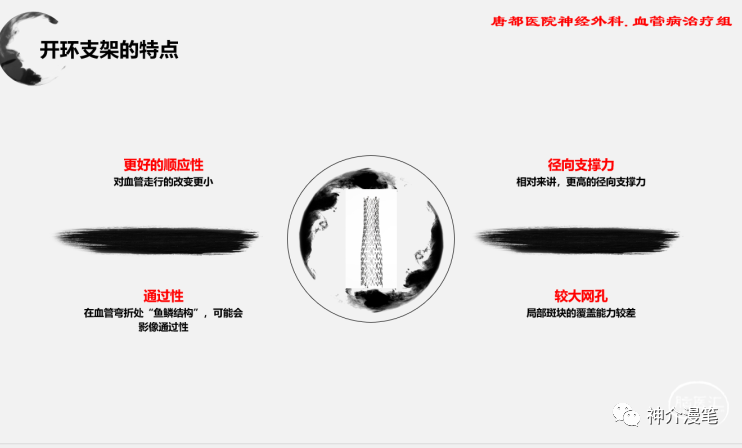

第一个概念:开环支架与闭环支架。开环支架有自己独立的支架单元,每个单元之间有少数几个连接点相连,这样能保证每一个支架单元的相对独立性。在弯曲迂曲,管径差异较大的血管条件下能保持更好的贴壁性。下图即为典型的开环支架设计,红色部分为支架单元之间的连接点,其余部分呈现为开放不连续状态。

下图为开环支架打开及释放的过程,可以看到每一环支架都会相对独立,而不会过多的影响其他部位打开的情况。所以对于好多新手,我会建议他们早期可以尝试开环支架的释放,因为头端一旦打开就会有比较良好的贴壁性,而不用担心支架滑落。

对于血管走形迂曲,管径差异较大,偏心性狭窄。预期支架贴壁困难时,首选开环支架。因为其独立支架单元的结构,更容易贴壁。下图所示,管径差异较大时,左图的闭环支架在狭窄局部贴壁不良,而右图的开环则有更好的贴壁性。

从其他角度讲,开环支架对于血管走形的改变会较小,能大体顺应血管走行。而闭环支架更多的趋势是趋于一根直棒棒,对于迂曲血管走行相对改变较大。其实很多情况下,我们并不希望血管的走行被改变过大。下图为闭环和开环释放后对血管走行改变的模式图,左图为闭环释放后血管的形态预测,整体的走行改变还是会大一些。

从上面这个简单的病例中可以看出,PRICISE支架对于血管局部走行的改变较小,基本顺延了原始的走行方向。这也是开环支架的一大优势。